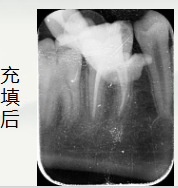

开髓后

依次使用

欧罗德卡 机用锉混号 的

开口锉15/08疏通锉15103过渡锉20/05成型锉25/06